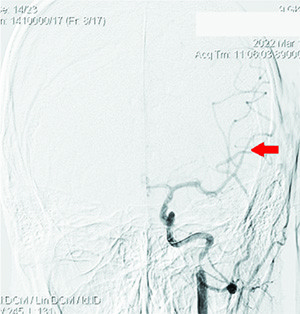

Проведена диагностика: определялась окклюзия несколько дистальнее устья ВСА слева, коллатеральное заполнение сосудов левой гемисферы из правой ВСА и позвоночных артерий, локальная окклюзия ветвей первого порядка левой СМА после бифуркации (см. рис. 2 и 3).

Принято решение о реканализации ВСА, механической тромбэкстракции из СМА слева. По проводнику селективно в ВСА установлен интродьюсер направляющий катетер Destination F7 (см. рис. 4 и 5).